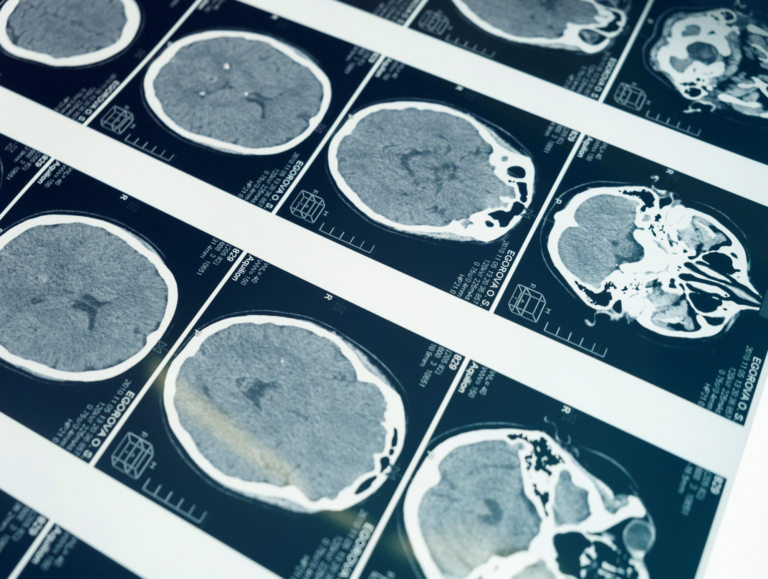

Badanie rezonansem magnetycznym, znane również jako MRI (z ang. Magnetic Resonance Imaging), to nieinwazyjna metoda diagnostyczna umożliwiająca uzyskanie szczegółowych obrazów wnętrza ciała — w tym narządów, tkanek, stawów oraz naczyń krwionośnych.

Technika ta opiera się na zjawisku rezonansu magnetycznego, które wykorzystuje silne pole magnetyczne i fale radiowe do tworzenia obrazów o wysokiej rozdzielczości.

• Dokładność: MRI daje bardzo szczegółowy obraz tkanek miękkich (takich jak mózg, mięśnie czy więzadła) i jest szczególnie przydatne w diagnostyce neurologicznej i ortopedycznej.